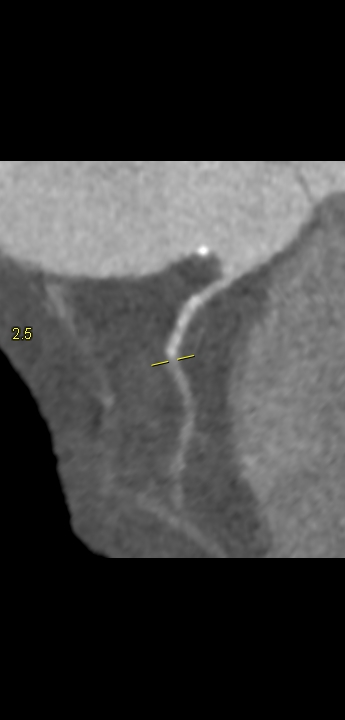

Video 1: cine reconstrucție axială din achiziția pentru scor de calciu